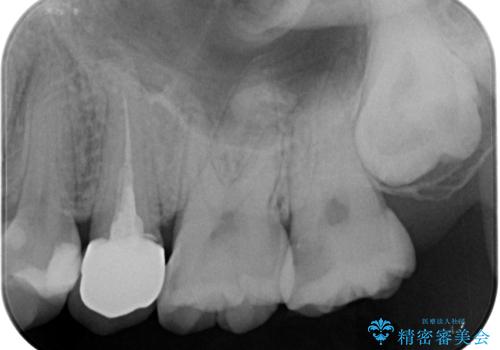

- 左上の前から5番目の金属の詰め物(メタルインレー)が取れたとのことで来院された患者様です。一時帰国中とのことで短期間での治療を希望されていました。土台はファイバーコアがしっかり入っていたため、そのまま利用することにしました。根管治療は症状もなく、レントゲン上でも病変を認めないため患者様と相談して根管治療を行わないことにしました。拡大鏡の視野下において、虫歯を除去して元々の詰め物の範囲も大きいためオールセラミッククラウンに適した形に整えました。

根管治療を施した歯は割れるリスクが上昇するため、詰め物(インレー)ではなく、被せ物(クラウン)にしなければなりません。

適合もよく、機能的に問題もなく、見た目も満足されていました。